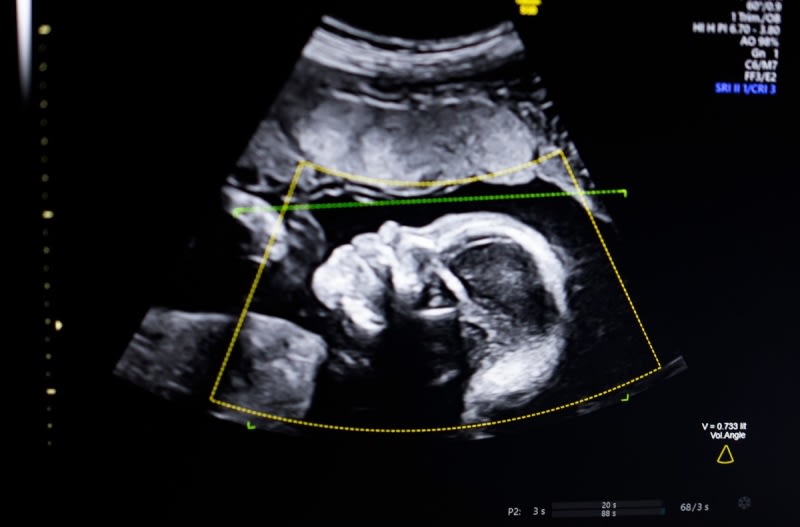

Biotics AI received FDA clearance for its computer vision AI software that detects fetal abnormalities in ultrasound images. The technology supports quality assessment, anatomical completeness, automated reporting, and clinical workflow integration. Trained on 11,000 diverse ultrasounds, the system aims to address poor prenatal